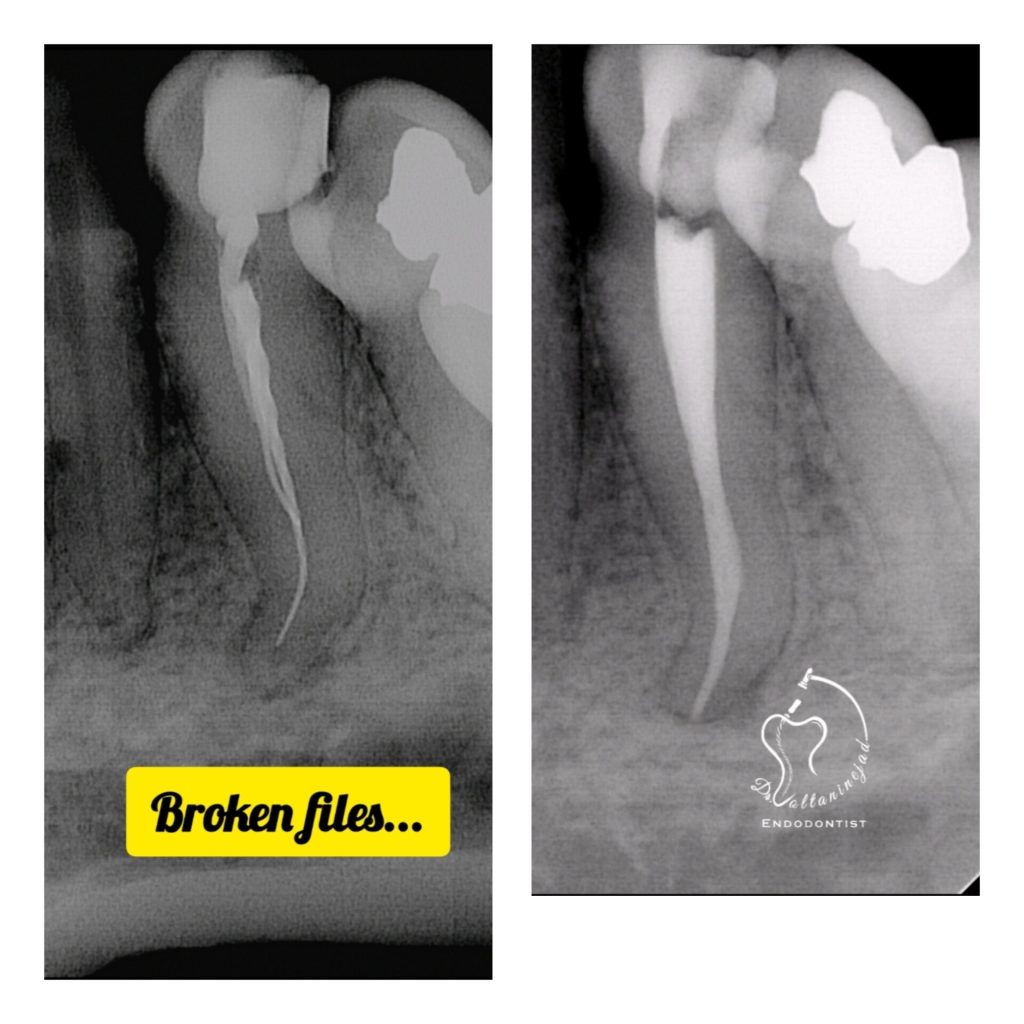

🔹 خارج کردن فایل شکسته از کانال

• شرح کوتاه: بیمار با درمان ریشه نامناسب و فایل شکسته در کانال مراجعه کرد. فایل با میکروسکوپ خارج شد و درمان ریشه مجدد انجام شد.

• نتیجه: رفع درد و حفظ دندان بدون نیاز به جراحی.

خارج کردن فایل شکسته